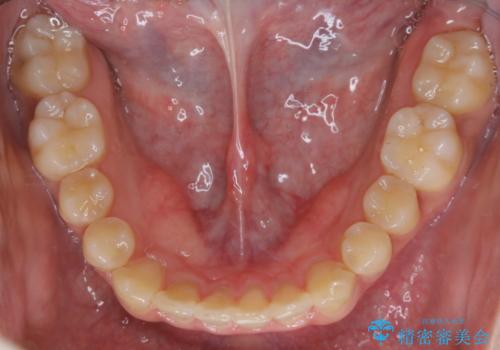

- 前歯のがたつきが気になるとご相談にいらした方です。左の奥歯の噛み合わせのズレも認められたため、インビザライン治療にて改善しました。

主訴である前歯のガタつきだけでなく、奥歯の噛み合わせからしっかり治療したため、治療期間が長めとなりました。患者様ご本人としては治療の途中で一時的にモチベーションが下がったこともあったようですが、最後まで頑張って続けて頂けたことで噛み合わせ及び見た目の改善を行うことが出来ました。